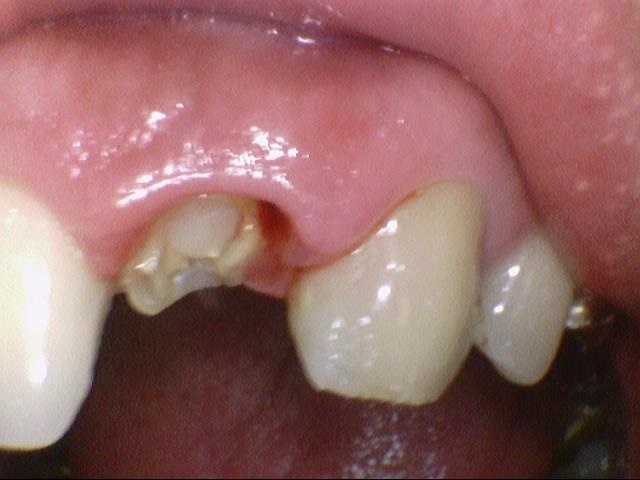

![[시청역/서울역 치과] 앞니 치아부러짐 자연스럽게 치료사례 관련 이미지 1](https://pub-9f2bb3498faf4d1d8714b41df24753e3.r2.dev/content/clinics/archive/rseeanjxfu/naver_blog/yonseiyegam/assets/by_hash/d423924e944a172afabe4390b46174eeeafc6704f921d50379a95cc08d5d4d36.jpg)

앞니가 깨져서 오셨을 때 처음 상태